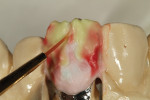

The restoration was tried on the model for a fit check (Figure 33). Cervical translucency powder was applied (Figure 34) in formula No. 24. Translucency neutral was then applied (Figure 35), and a line was drawn down through the porcelain in order to create a crack line with a white stain (Figure 36). The restoration was baked again at 780°C (Figure 37), and the interproximal contact was checked on the model (Figure 38).